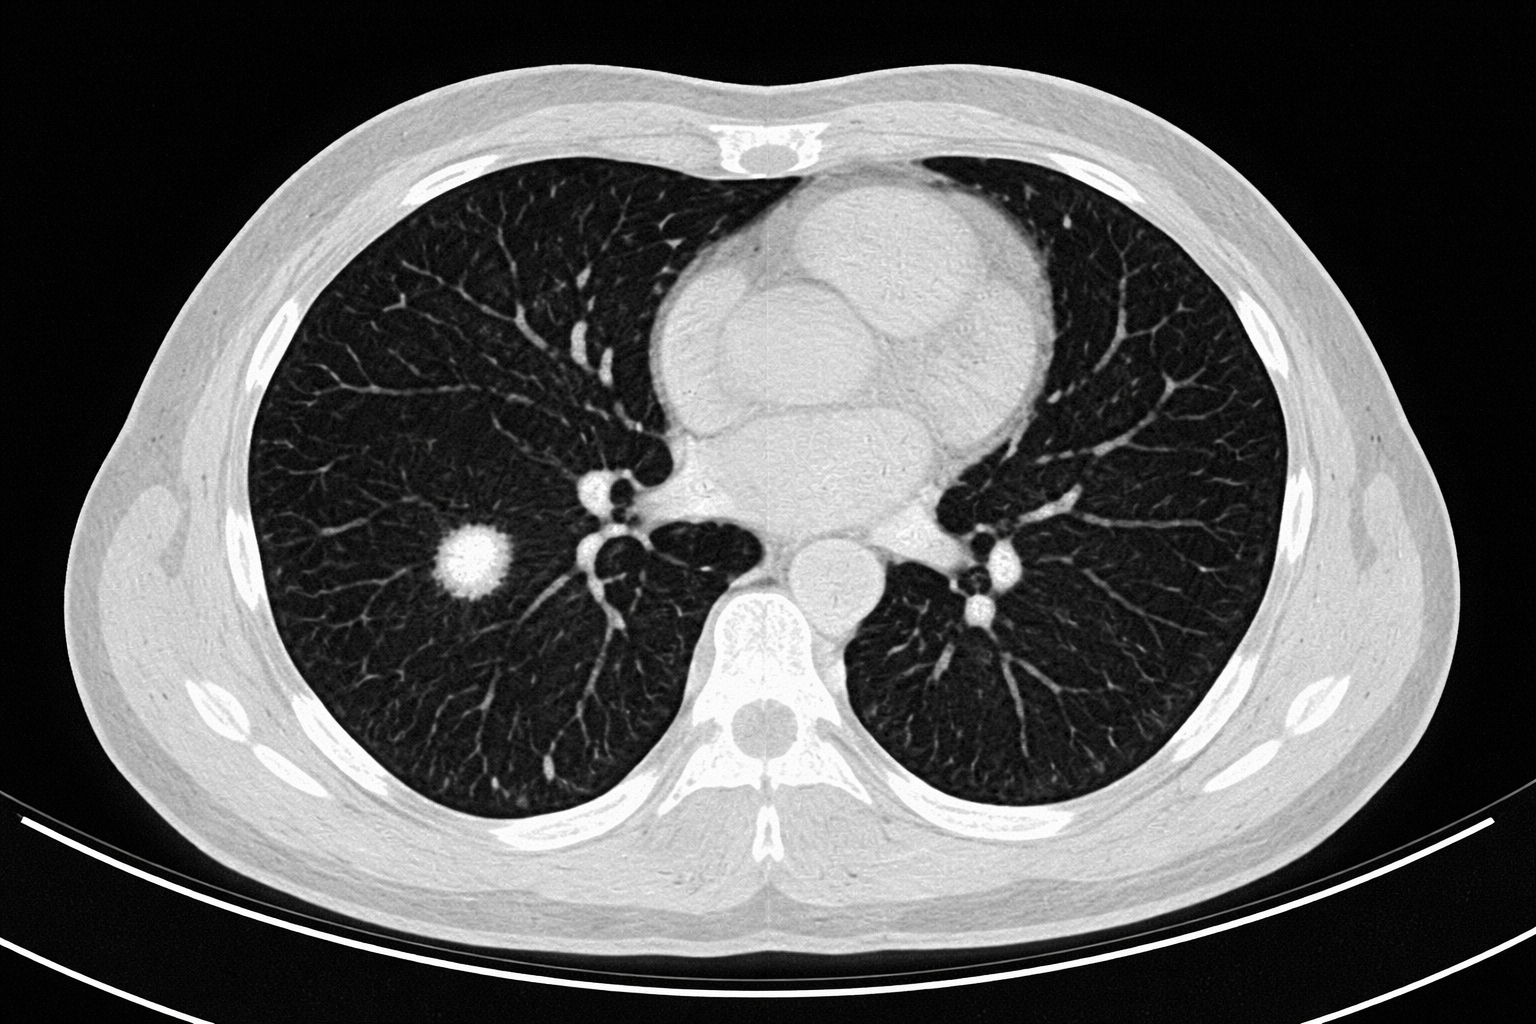

Incidental Pulmonary Nodules: Differentials and Diagnostic Imaging

Incidental pulmonary nodules are common, and often anxiety-provoking. This post walks through a practical, evidence-based approach to risk stratification, imaging interpretation, and follow-up, tailored for primary care clinicians.

Read time: 7-8 minutes